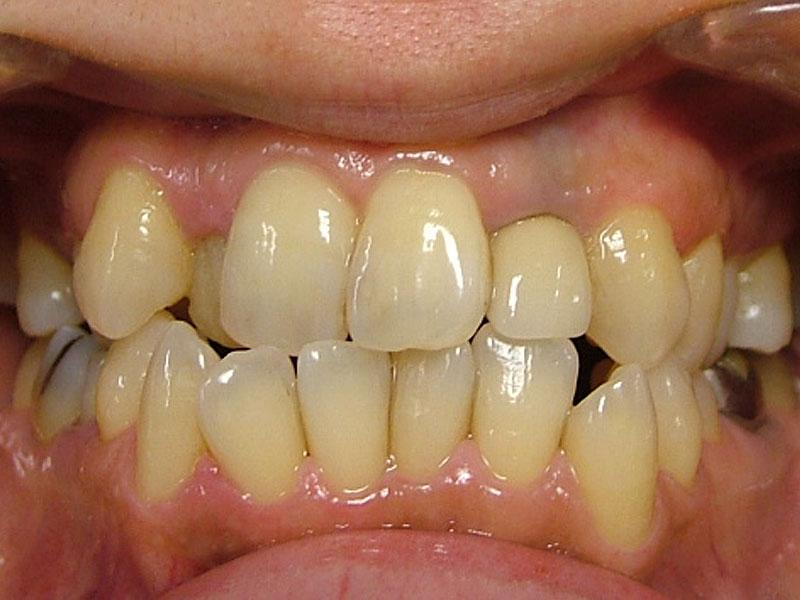

術前

術後

約2年治療期間で包括矯正治療は完結となり、患者さんは大変満足してくれました。更にかみしめ癖も軽減し、肩こりも無くなったとのことです。口腔内写真からも舌房が確保され、舌圧痕がなくなり、かみしめ癖が軽減したことも十分にわかります。